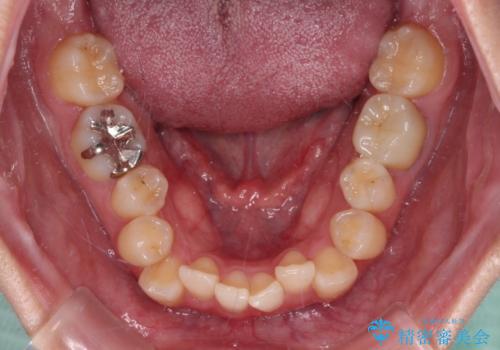

- 前歯のクロスバイトを改善したいとのことで来院された患者様です。

マウスピース矯正では前歯の神経への負担が大きいことを懸念され、ワイヤー装置による矯正治療を行うこととしました。

クロスバイトが改善する際は、前歯しか接触しないため、痛みがあったり食事が取りにくかったりと、不便な時期がありますが、1年強の短期間で無事に治療を終えることができました。